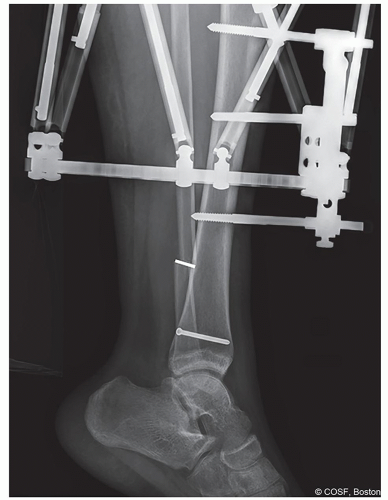

Principles of external fixator stability are of critical importance in distraction osteogenesis. Stability increases with larger pin diameters, greater pin spread (on each side of osteotomy), increased pin number, and pins in multiple planes. Fine wires should be spread as close to 90° as anatomically possible, and at least 60° is preferable

Proper pin/wire insertion technique is critical to minimize the risk of postoperative infection. This includes placement of half-pins on subcutaneous bone borders (if possible), adequate skin incisions for pin placement, use of sharp drill bits (flutes of drill should be cleaned between uses) and irrigation to prevent thermal necrosis, and use of soft tissue protector when drilling to prevent soft tissue injury

Pins/wires should remain 15 mm from knee joint and 10 mm from ankle joint to avoid intracapsular placement

Half-pin diameters of 5 mm or 6 mm are preferred in the lower limb (but pin diameter should not exceed 1/3 the diameter of the bone). Pins with hydroxyapatite (HA) coating adhere better to bone and may lead to less frequent loosening and pin-site infection